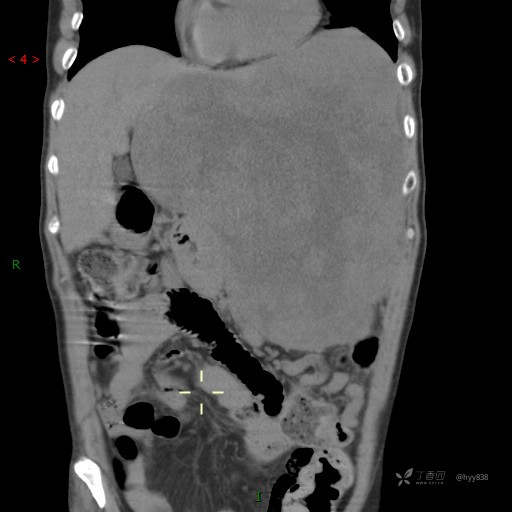

讨论:病变来源?病变性质?